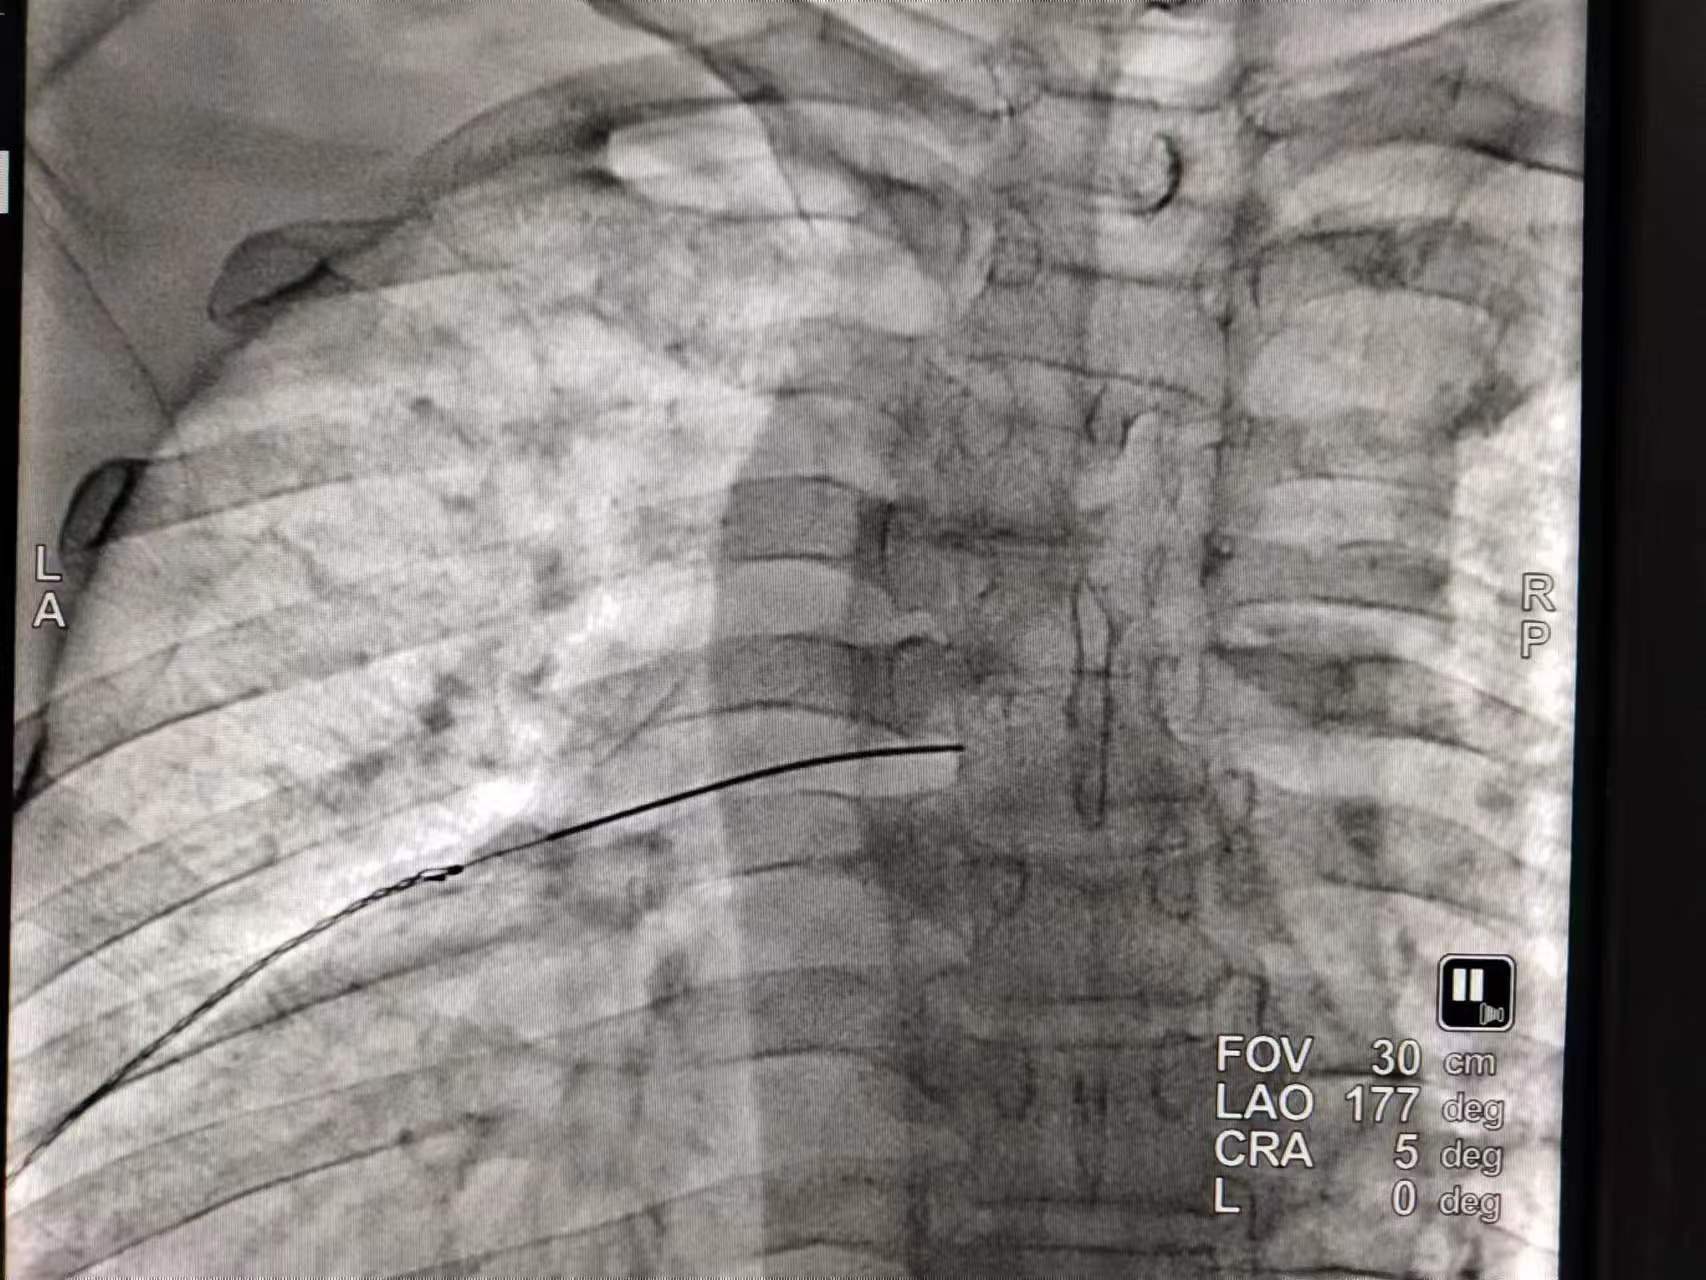

神經(jīng)射頻治療是在超聲或DSA引導(dǎo)下將射頻針穿刺至責(zé)任神經(jīng)的周圍利用電流電壓刺激的方式,調(diào)節(jié)神經(jīng)電位,從而起到治療疼痛的作用。

胸背根神經(jīng)結(jié)射頻治療圖像。(供圖)

脊髓電刺激是在C臂引導(dǎo)下,使用穿刺針穿刺至脊椎硬膜外,將刺激電極沿著椎管硬膜外一直向上放置到目標(biāo)位置,給予持續(xù)的低頻電流刺激14天左右??梢云鸬阶钄嗤从X(jué)傳導(dǎo)和改善循環(huán)的作用,促進(jìn)神經(jīng)修復(fù)的作用。